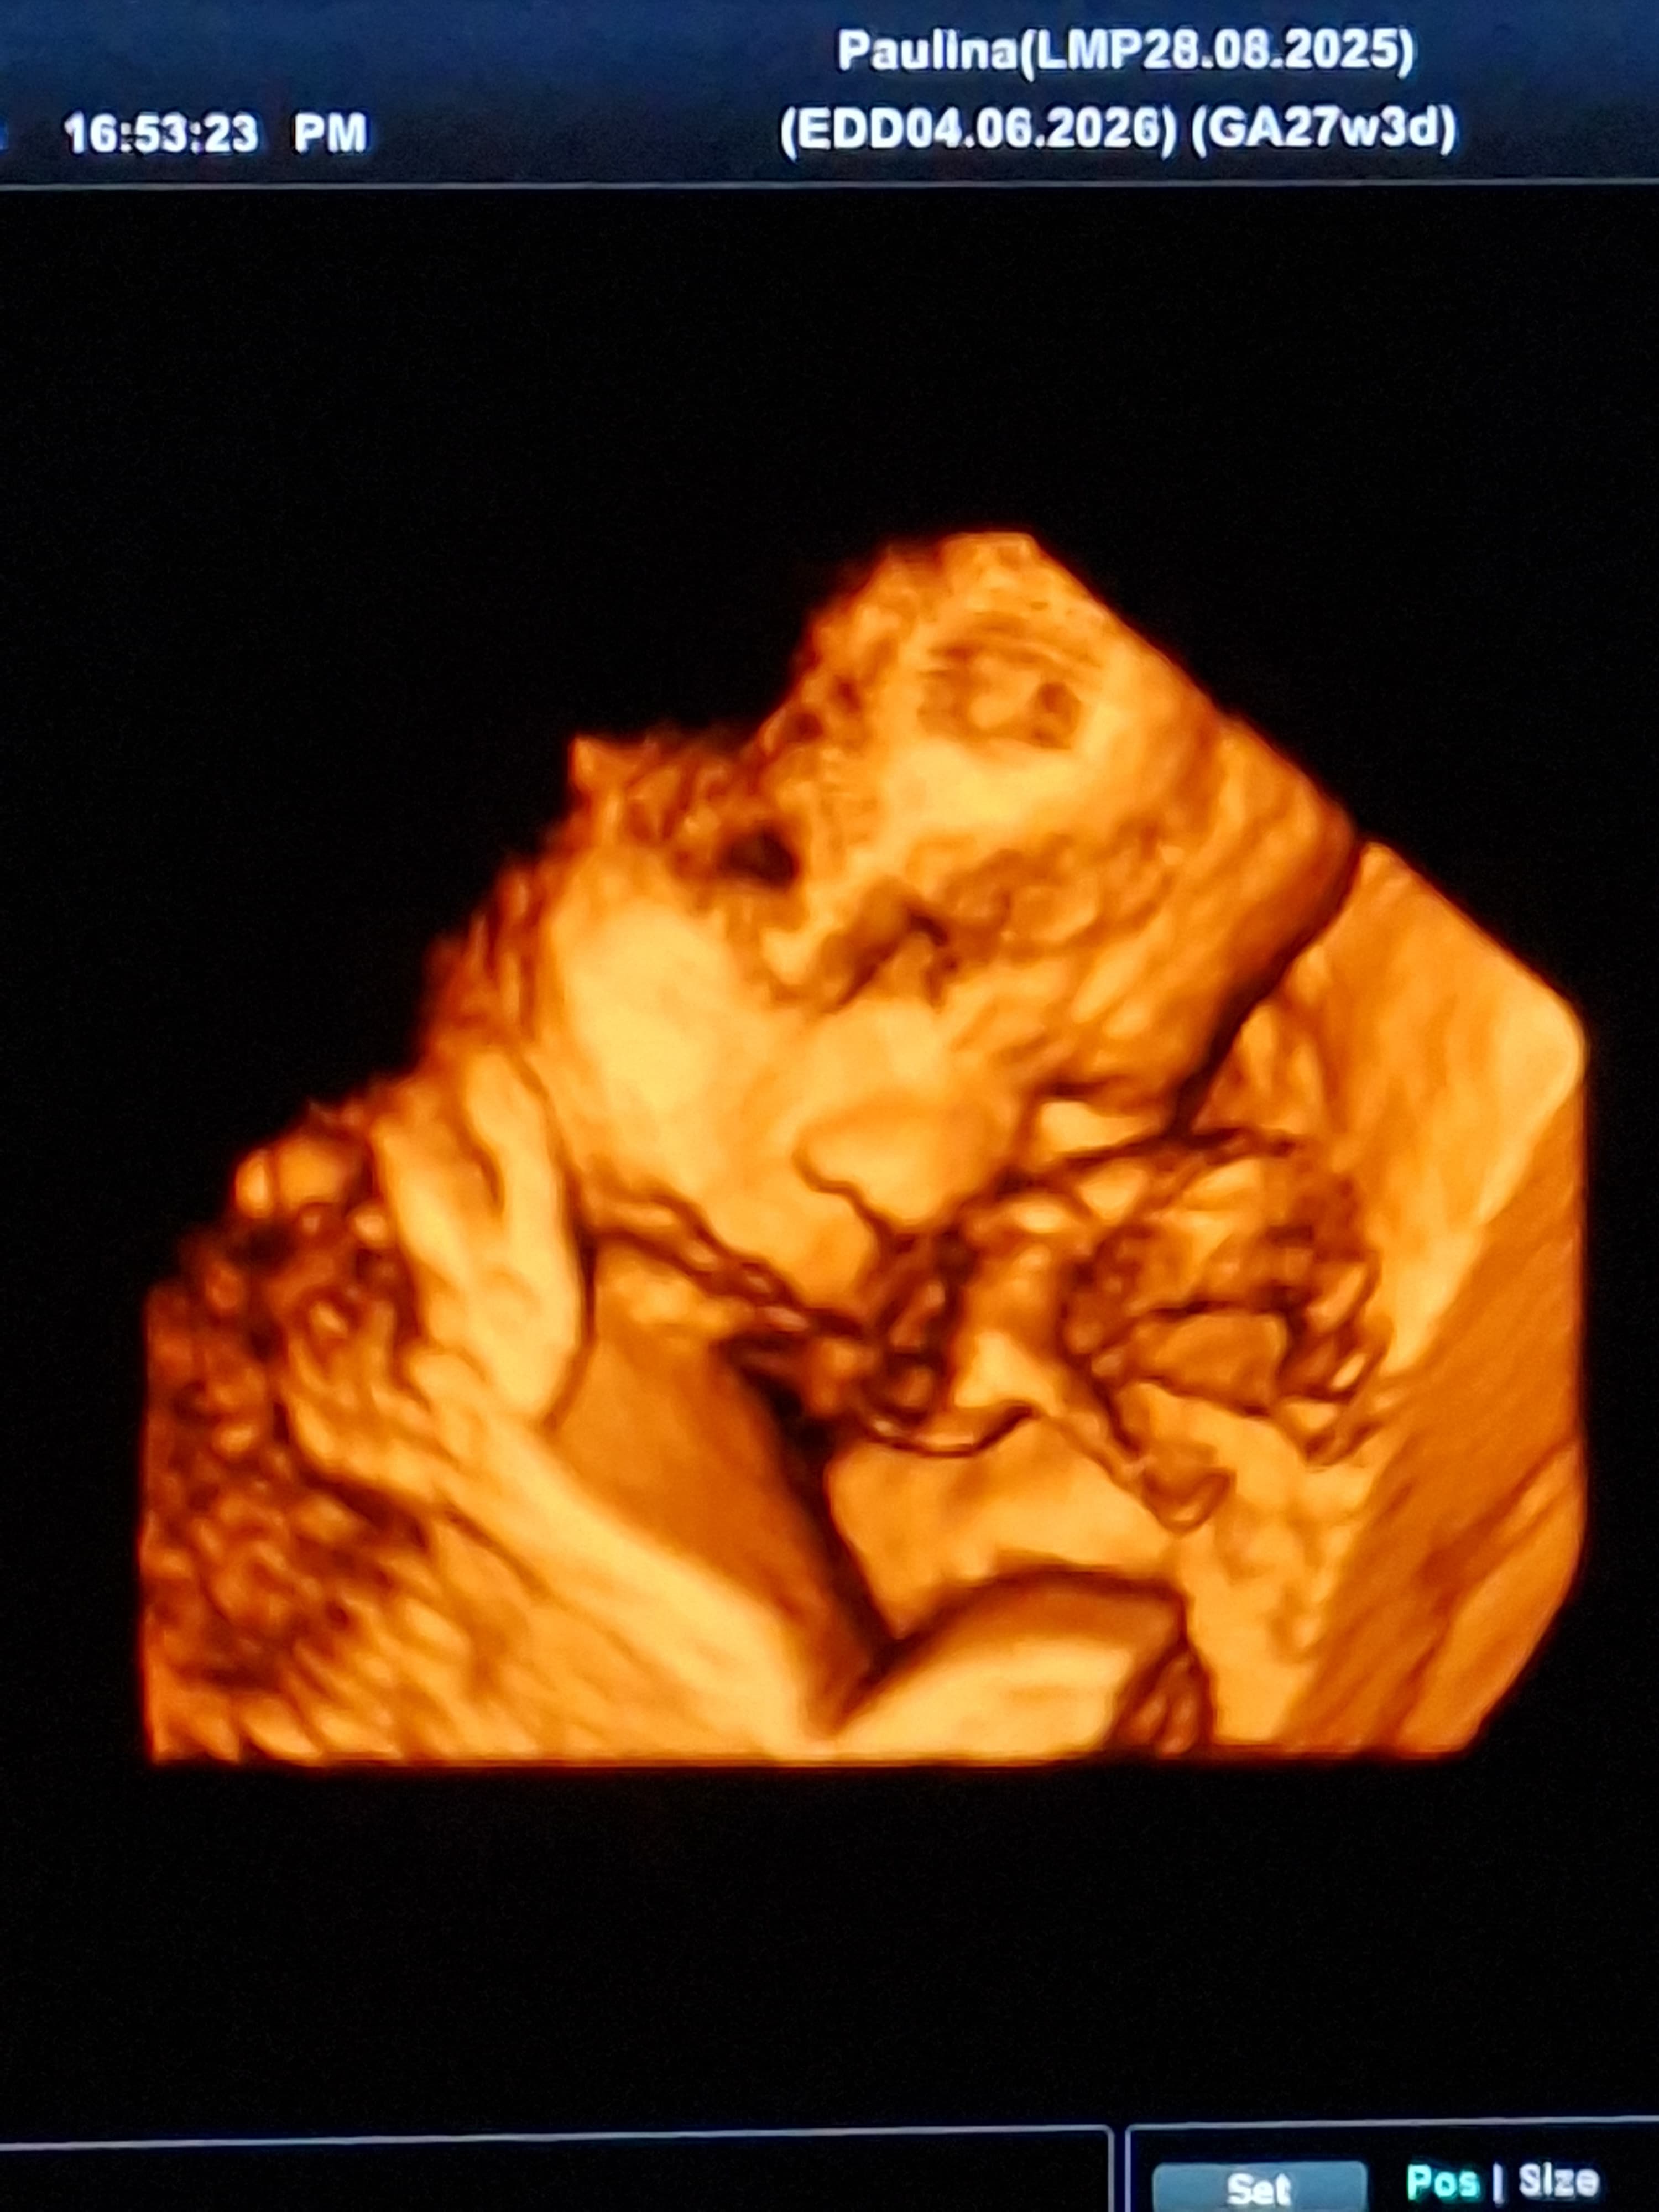

Ja wczorajszy Dzień Kobiet spędziłam m.in. na USG 😊 Udało nam się zobaczyć śpiącego Małego w 3D. Spał sobie słodko z głową na łożysku, dwie łapki obok siebie 🥹

https://zapodaj.net/plik-DPmoSlPsI2

Niestety, żeby nie było tak kolorowo, wyszło lekkie poszerzenie jednej nerki. Na razie tylko do obserwacji w kolejnych badaniach i mamy być pod dodatkową opieką w pracowni USG. Trochę się zmartwiłam, bo moja mama też miała problemy z nerkami. Ale mąż mnie uspokaja, że podobno w 90% takie rzeczy same się normują.

ZiarnoCzasu wrote:Ja wczorajszy Dzień Kobiet spędziłam m.in. na USG 😊 Udało nam się zobaczyć śpiącego Małego w 3D. Spał sobie słodko z głową na łożysku, dwie łapki obok siebie 🥹